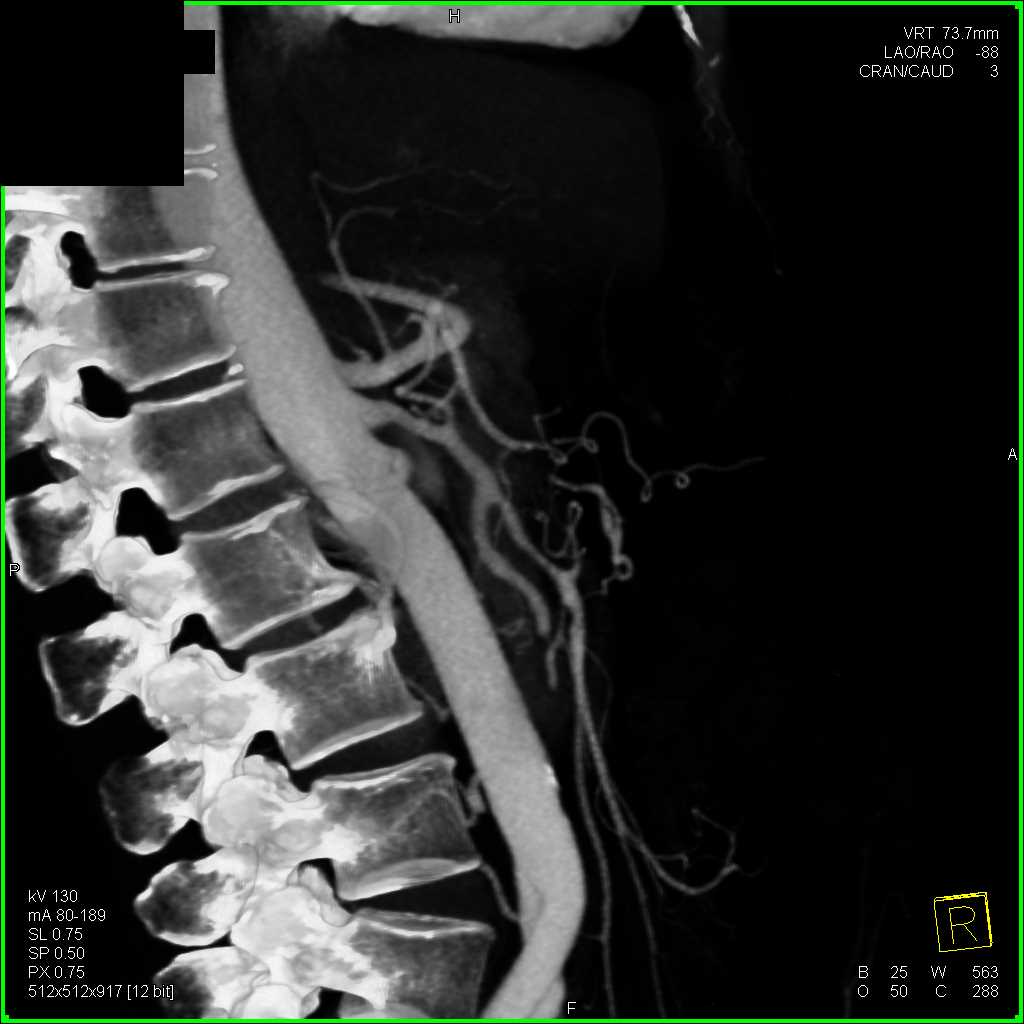

Neuroendocrine Tumor Body of Pancreas